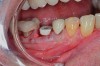

Case Presentation

A mandibular right first molar was extracted due to an advanced Class III furcation and an irreversible pulpitis—a combination lesion. An immediate implant placement protocol was elected, and a PEEK abutment was placed on the implant (Figure 1). After 3 months of healing, a scan body was placed on the osseointegrated implant (Figure 2 and Figure 3), and an intraoral scan was taken (TRIOS Pod) (Figure 4) for the fabrication of a screw-retained crown.

Once the STL file generated from the intraoral scanner was sent to the laboratory (Figure 5), the technician used proprietary software to design the crown (Figure 6 through Figure 8), mill the crown, and digitally print a SLA model (Dental SG, Formlabs, www.formlabs.com) (Figure 9 through Figure 11), and then finish the crown on the digitally printed model. The angulated screw-channel full-zirconia crown (Nobel Biocare) (Figure 12) was seated, and contacts were evaluated intraorally and adjusted extraorally. The screw-retained crown was torqued to 35 Ncm2, and the screw access was sealed (Figure 13 through Figure 15).

Fig 3. Confirmation of seating of scan body.

Figure 3

Fig 13. Screw-retained implant crown replacing missing first molar, occlusal view (Fig 13) and buccal view (Fig 14).

Figure 13

Fig 14. Screw-retained implant crown replacing missing first molar, occlusal view (Fig 13) and buccal view (Fig 14).

Figure 14

Fig 15. Final restoration of mandibular right first molar.

Figure 15